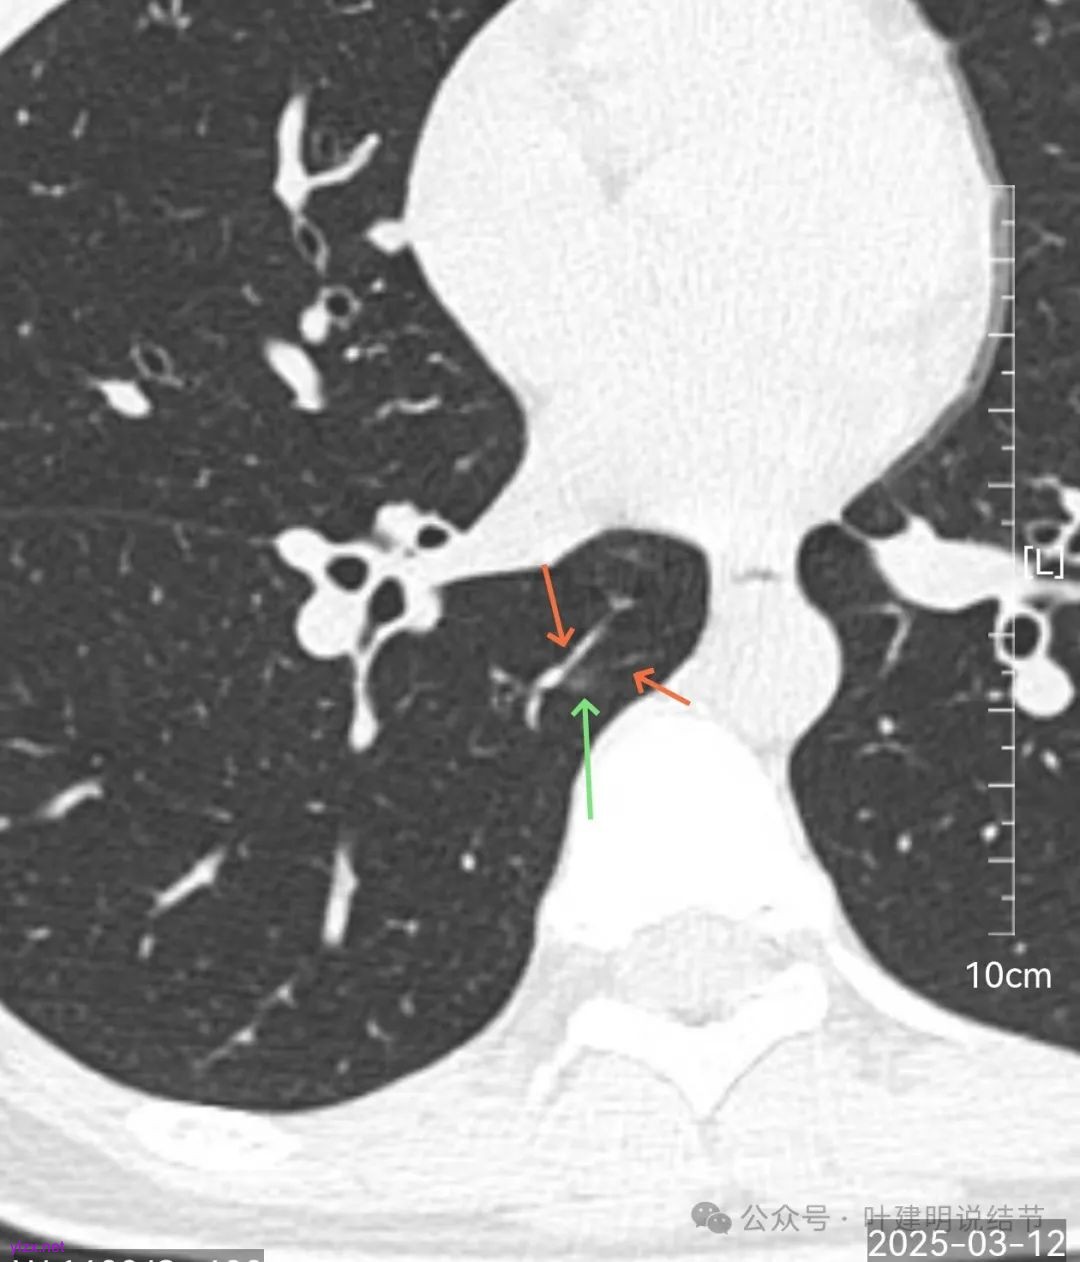

再来看风险最大的病灶6的连续层面:

血管从旁过,没有受结节影响。